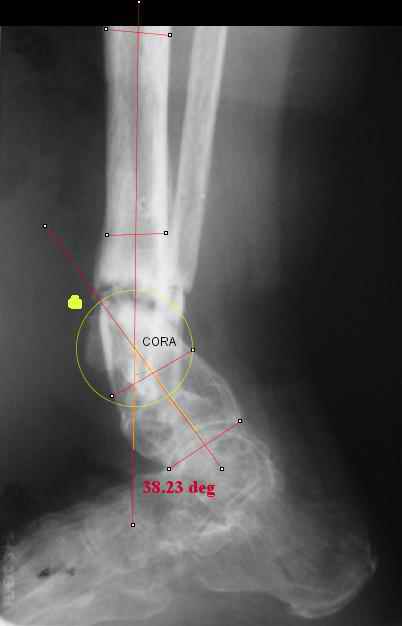

TDVC> I played with your image using some orthopedic software

TDVC> we have been developing for digital image analysis.

TDVC> a correction around the CORA through the old # will restore

TDVC> alignment without much translation.

Maybe my "embedded software" is obsolete but it hints me to place hinges at the yellow point - this must result with alignment and some lengthening without translation. What do you think?